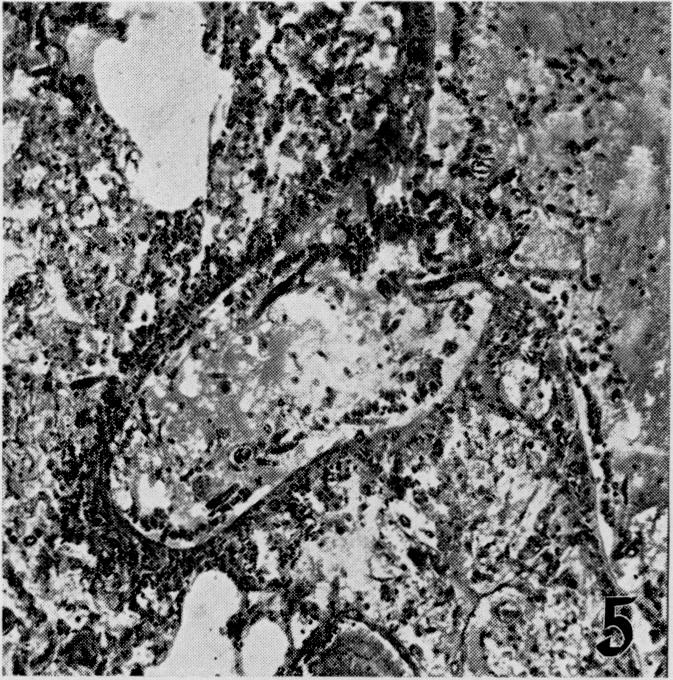

The effects of metabolic alterations on experimental Rhizopus oryzae (mucormycosis) infection.

Yale J Biol Med. 1956 Sep;29(1):23-32.